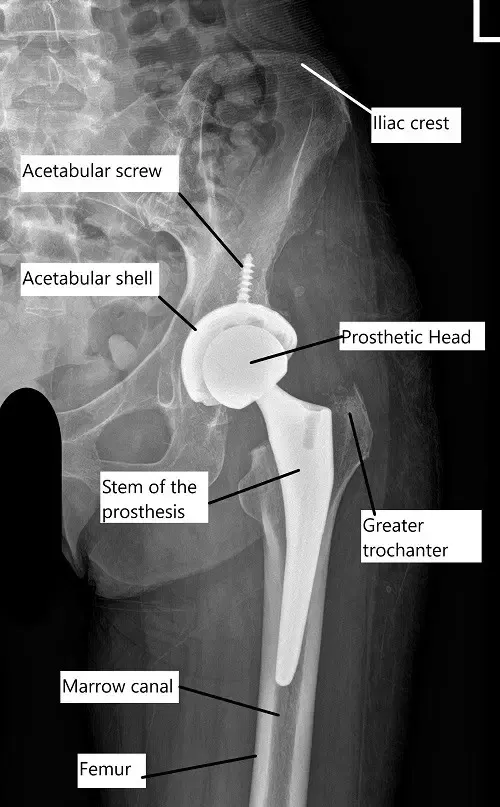

X-ray showing a total hip replacement